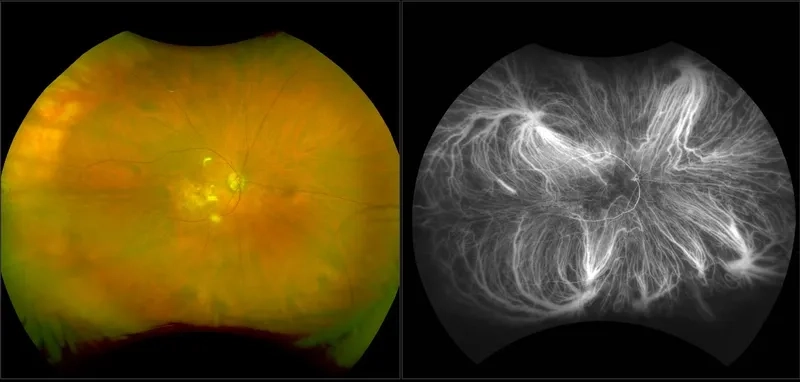

Advanced stage of proliferative diabetic retinopathy